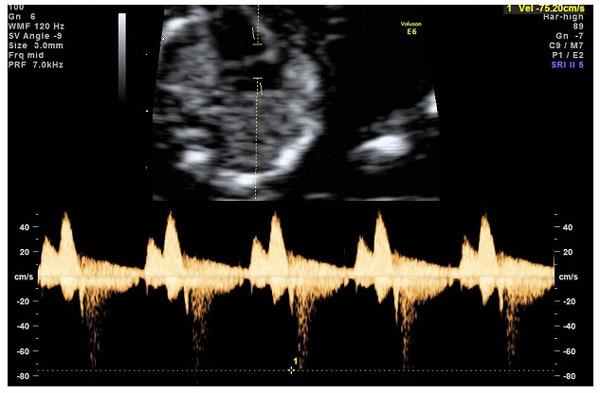

- кровоток через трикуспидальный клапан в сердце плода. Здесь ретроградный (обратный) кровоток тоже указывает на хромосомную патологию, либо может проявляться при врожденных пороках сердца.